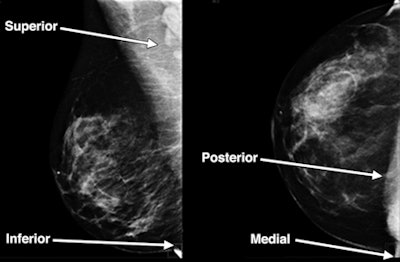

Conebeam CT had better breast tissue coverage for the lateral, medial, and posterior imaging aspects (92.5% versus 12.5%, 90% versus 35%, and 90% versus 52.5%, respectively), while mammography performed better than conebeam CT in the axilla and axillary tail aspects (72.5% versus 7.5%).

| Images are of a 47-year-old woman with a sonographically proven 0.8-cm benign cyst. Above: Mediolateral oblique (left) and craniocaudal (right) digital mammograms do not clearly show a benign cyst. Below: Sagittal and transverse conebeam breast CT images corresponding to the images above show a benign cyst differentiated from surrounding breast parenchyma owing to lack of structure overlap. Images courtesy of the American Roentgen Ray Society. |